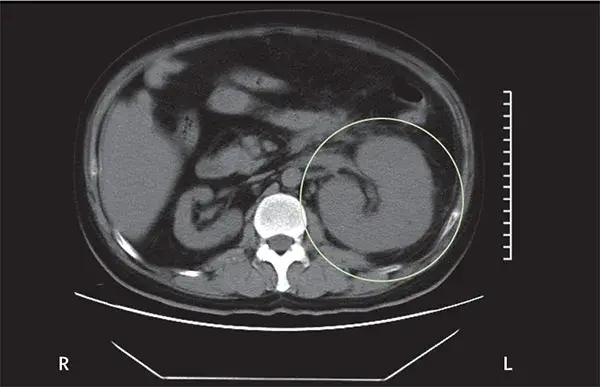

Caso muy ilustrativo publicado en Kidney 360 (enlace). Paciente de sexo femenino de 43 años con antecedentes de nefritis lúpica (NL) proliferativa durante 13 años. La paciente tenía un historial de enfermedad grave, con múltiples tratamientos que incluyeron infusiones de metilprednisolona y ciclofosfamida debido al compromiso del sistema nervioso central (SNC) y de la NL.